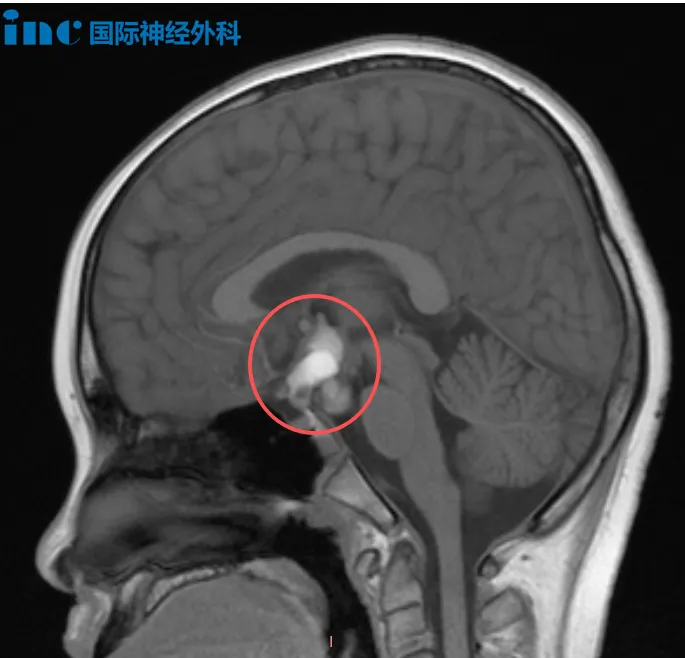

2、12岁男孩颅咽管瘤

涛涛今年8月因头痛查出颅咽管瘤,20mm×15mm×27mm大小的病变已经让脑干受压后移。“肿瘤已经压迫到视交叉后方的视路系统,这说明肿瘤在机械性地造成视功能障碍。如果手术一再推迟,这种压迫会导致视路受到进一步损伤,甚至可能出现永久性的视野缺损……”面对中药与偏方疗效不佳、孩子自觉症状加重、生长激素也出现问题的现实,巴教授对病情风险的评估也让家长意识到,手术是避免肿瘤进一步恶化、为孩子争取未来的唯一选择。